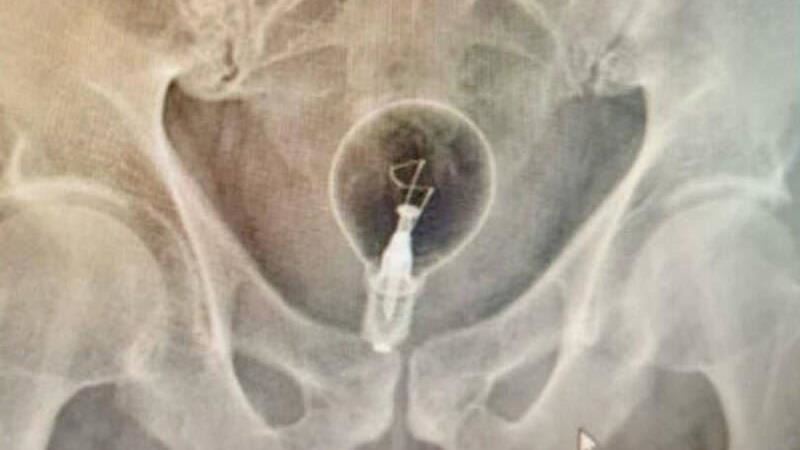

義大利近期出現一起罕見病例,一名85歲老翁,日前因肛門劇烈疼痛就醫,結果醫師照X光後發現,老翁的直腸內竟塞了一顆燈泡,因為拿不出來,只好到醫院求救,最後在醫師協助下順利取出燈泡,化解危機。由於老翁並未告知為何要塞燈泡,醫師推測對方很可能在進行「色情實驗」。

由於老翁就診時,只向醫師表示體內有異物,醫師照了X光才發現老翁體內竟有一顆「完整燈泡」,離譜狀況讓現場醫護人員全傻眼,最後醫師使用手術鉗將燈泡完好無缺的取出,老翁則因直腸受傷住院觀察,幸好無大礙。醫師表示,老翁並未透露為何要「塞燈泡」,但他們推測老翁很可能在進行「色情實驗」。